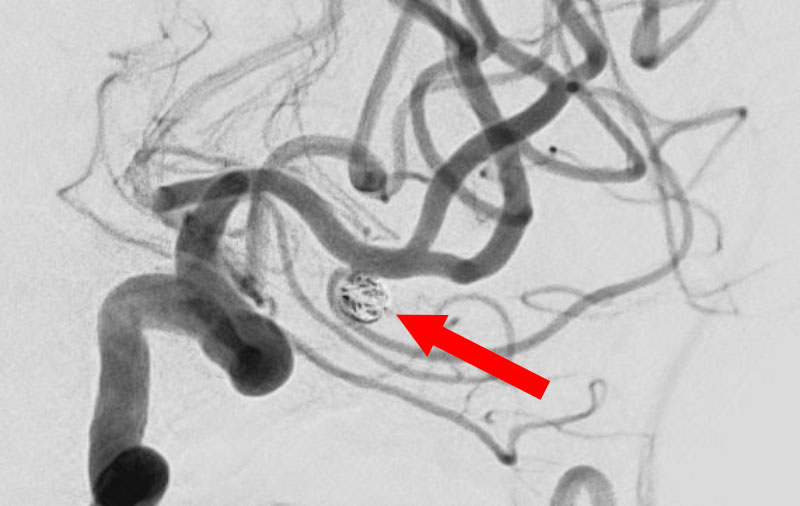

No.1593 手術中